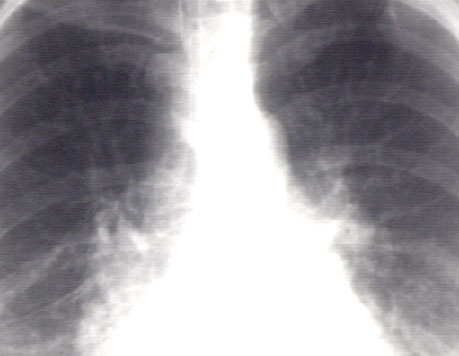

Left atrial enlargement & right ventricular enlargement

Further review of the PA view demonstrates additional important findings.

In this enlargement of the hilar region, engorgement of the upper lobe veins is well seen, a finding typical of pulmonary venous hypertension.